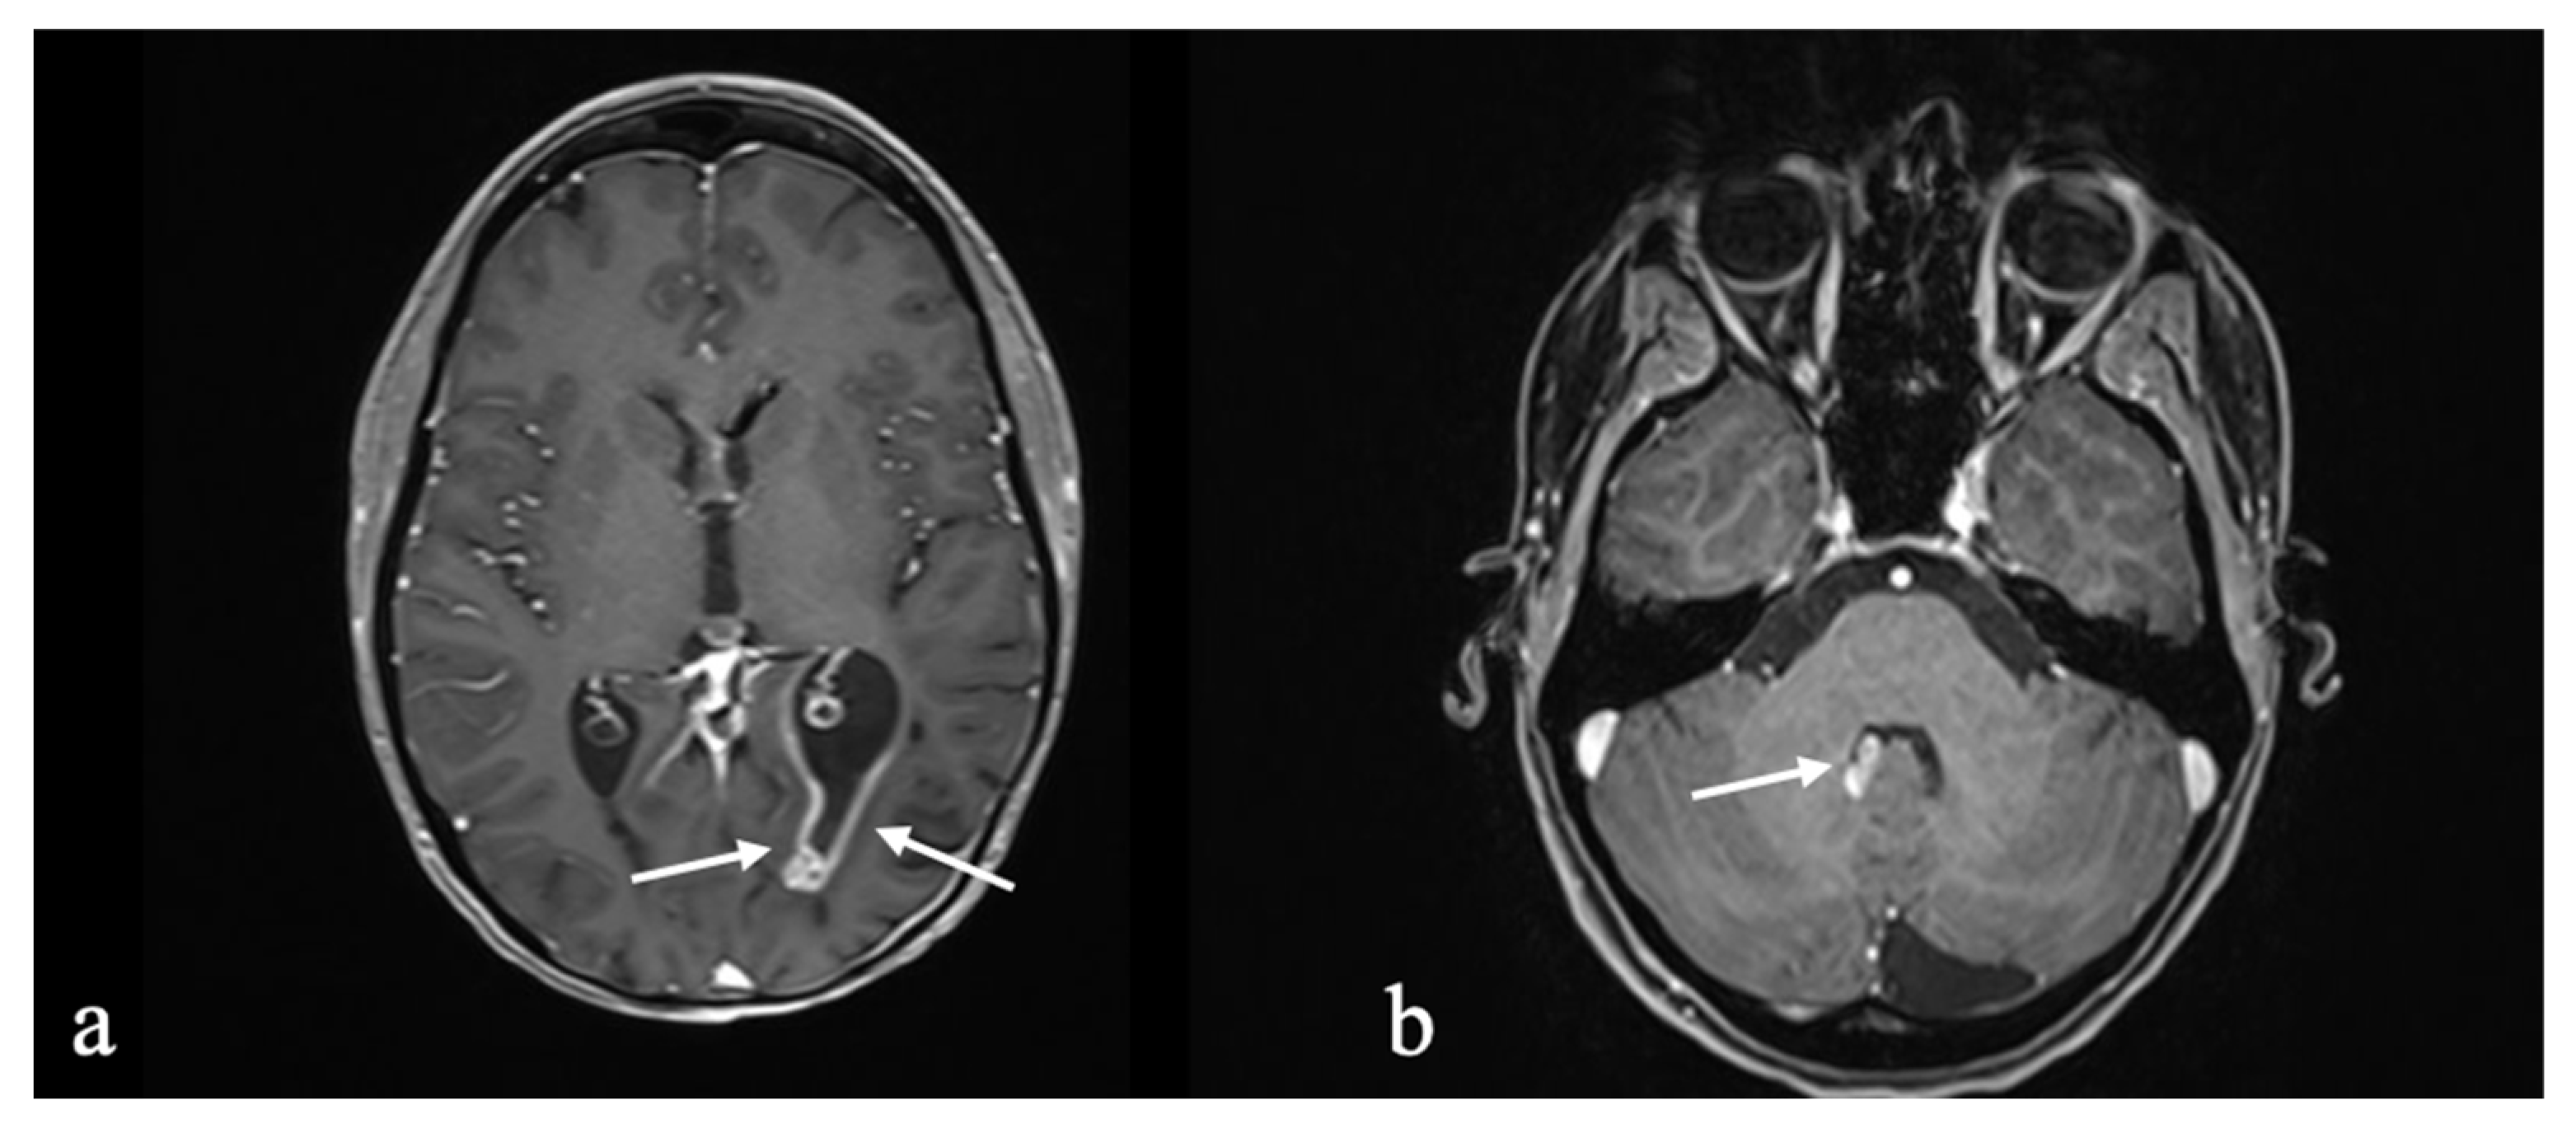

3.2. Case 2: Astroblastoma

3.2.1. Initial Diagnosis

3.2.2. Molecular Profiling and Treatment Timeline